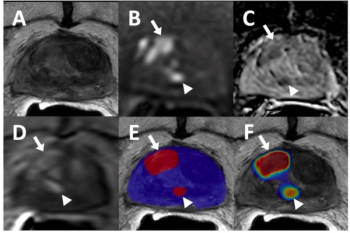

Utilizing a deep learning-based AI algorithm to differentiate between diagnostic and non-diagnostic quality of prostate MRI facilitated a 10 percent higher specificity rate for diagnosing extraprostatic extension on multiparametric MRI, according to research presented at the recent RSNA conference.